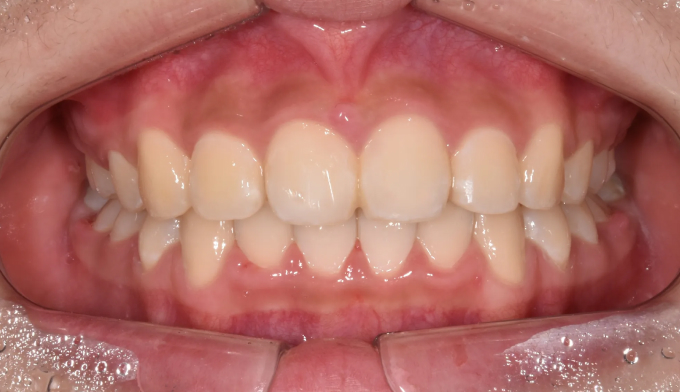

위턱, 아래턱 모두 치아 배열 공간이 부족한 경우 입니다.

확장장치를 이용해 공간 부족을 해결하고 치열을 배열하면 간단히 끝낼 수 있습니다.

이때 입술의 두께나 위치, 위아래 앞니의 각도를 종합적으로 고려하여야 합니다.

치아를 배열한다고 앞니가 뻐드러지면 잘못된 교정치료입니다.

총 치료기간은 20개월 소요되었습니다.